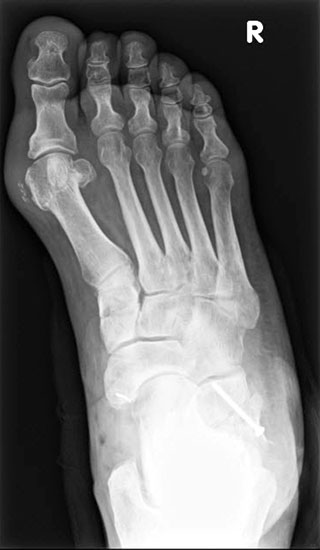

Konventionelles Röntgen

Stehende konventionelle Röntgenbilder eines Fußes mit Planovalgus Deformität Stadium II b dorsoplantar (dp) und seitlich. Auf der dp-Aufnahme zeigt sich die talo-calcaneare Divergenz, der gegenüber dem Kalkaneus nach anterior gleitende Talus und d

Stehende Aufnahmen des Fußes dorsoplantar (dp) und seitlich sowie des OSG anteroposterior (ap) sind die Grundlage der konventionellen Röntgendiagnostik (Abb. 5). Ergänzend werden gelegentlich die Rückfuβ-Alignement Aufnahme nach Saltzman 19 und Vergleichsaufnahmen der Gegenseite durchgeführt.

Der Talo-Metatarsale I Winkel bzw. die laterale talonaviculare Subluxation auf der stehenden dorsoplantaren Aufnahme des Fuβes dokumentieren das Ausmaβ des Vorfuβ abductus (Abb. 6 a,b). Ein dp Talo-Metatarsale I Winkel von > 10° (nach medial konvex) ist als pathologisch anzusehen. Mit der Bestimmung der talocalcanearen Divergenz (Abb. 6 c) erhält man ein Eindruck über das Ausmaβ des Rückfuβ valgus; eine leichte Divergenz bis ca. 12° gilt als physiologisch 20.

Auf der seitlichen, stehenden Aufnahme des Fußes wird ebenfalls der laterale Talo-Metatarsale I Winkel (Abb. 6 d) gemessen und so das kollabierte mediale Längsgewölbe dokumentiert. Auch hier gilt ein Talo-Metatarsale I Winkel von > 5° (nach plantar konvex) als pathologisch 21. Der Kollaps findet dabei meist im Talonaviculargelenk, seltener in der Naviculocuneiform-Gelenkreihe statt. Instabilität und Arthrose im 1. TMT sollten ausgeschlossen oder bei der Operationsplanung mit einbezogen werden. Weitere wichtige radiologische Messungen zur Beurteilung der Planovalgus-Statik und Progression der Deformität sind der laterale talo-calcaneare Winkel (Abb. 6 e) und der Abstand des Os cuneiforme-Unterrandes zum Untergrund (Abb. 6 f, Cuneiform height, 22. Eine anteriore Translation des Talus auf dem Kalkaneus findet man sowohl auf der ap, als auch auf der seitlichen Aufnahme des Fuβes mit Aufhebung der Cima-Linie.